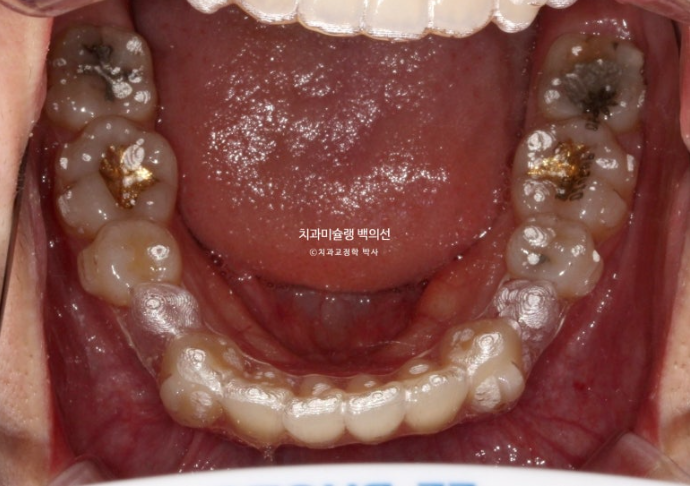

25년 5월까지 1년 10개월간 85개 장치를 모두 낀 후 모습입니다.

25.05

중심선은 잘 맞으며

앞니사이 공간이 조금 남아있습니다.

어금니 교합은 좋은 편

미세하게 남은 발치공간을 없애기 위해 추가장치 제작에 들어갑니다.

추가장치 갯수는 11개이며 25년 6월부터 9월까지 꼈습니다.